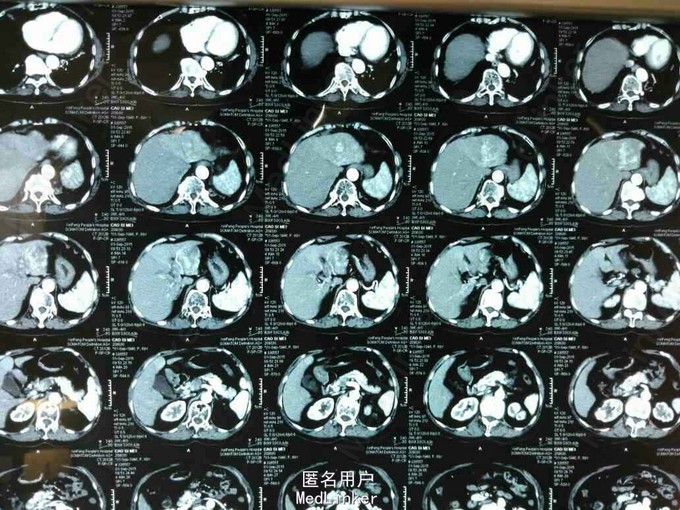

患者,女性,69岁,因“右上腹疼痛不适2月余”入院。

查体无特殊。辅查:腹部增强CT提示肝左外叶癌。AFP:92948ng/ml。

诊断:原发性肝左外叶癌。治疗:肝癌切除术。

随访:术后患者恢复好,嘱患者出院1个月后返远复查。讨论:该患者肿瘤局限于左外叶,肝功能较好,选择手术治疗,术后视情况是否需要TACE。